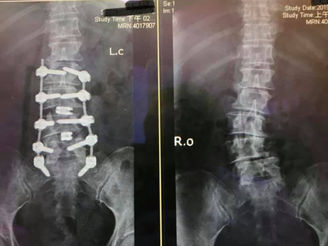

脊椎側彎診治--讓婆婆自己走路去買菜

78歲的獨居老婆婆,小孩都很孝順但她住不慣外地生活,一個人住在老家。無法活動讓她的子女每週買菜去給她,但阿嬤最大的希望是想自己走路,也不想再疼痛了。 脊椎側彎是非常困難的手術,尤其是年紀大的病患。最後一切順利平安,年紀大了,不痛就好。願上帝保守她!術後一個月她竟然自己走進我...